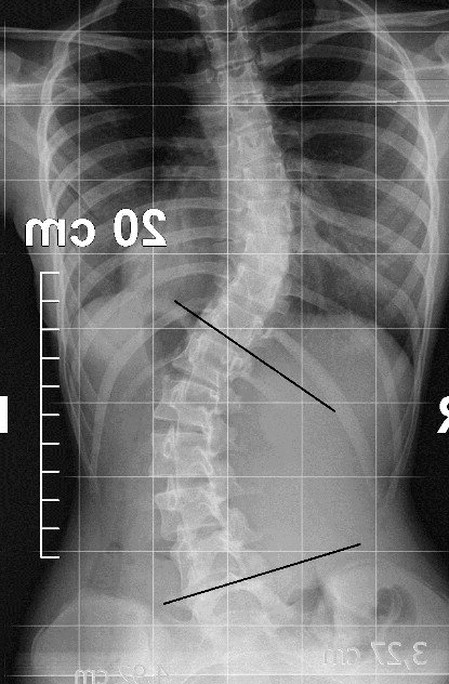

Immagine di supporto: esempio di materiale/visualizzazione dal tuo archivio (fisionet.eu).

Anamnesi mirata, obiettivi, test essenziali. Se disponibili: referti/RX per contestualizzare.

Immagini dal tuo archivio: esempi di seduta, materiale informativo e riferimenti utili al follow‑up.

Esempi visivi e strumenti: raccolta feedback, re-test e documentazione del percorso.